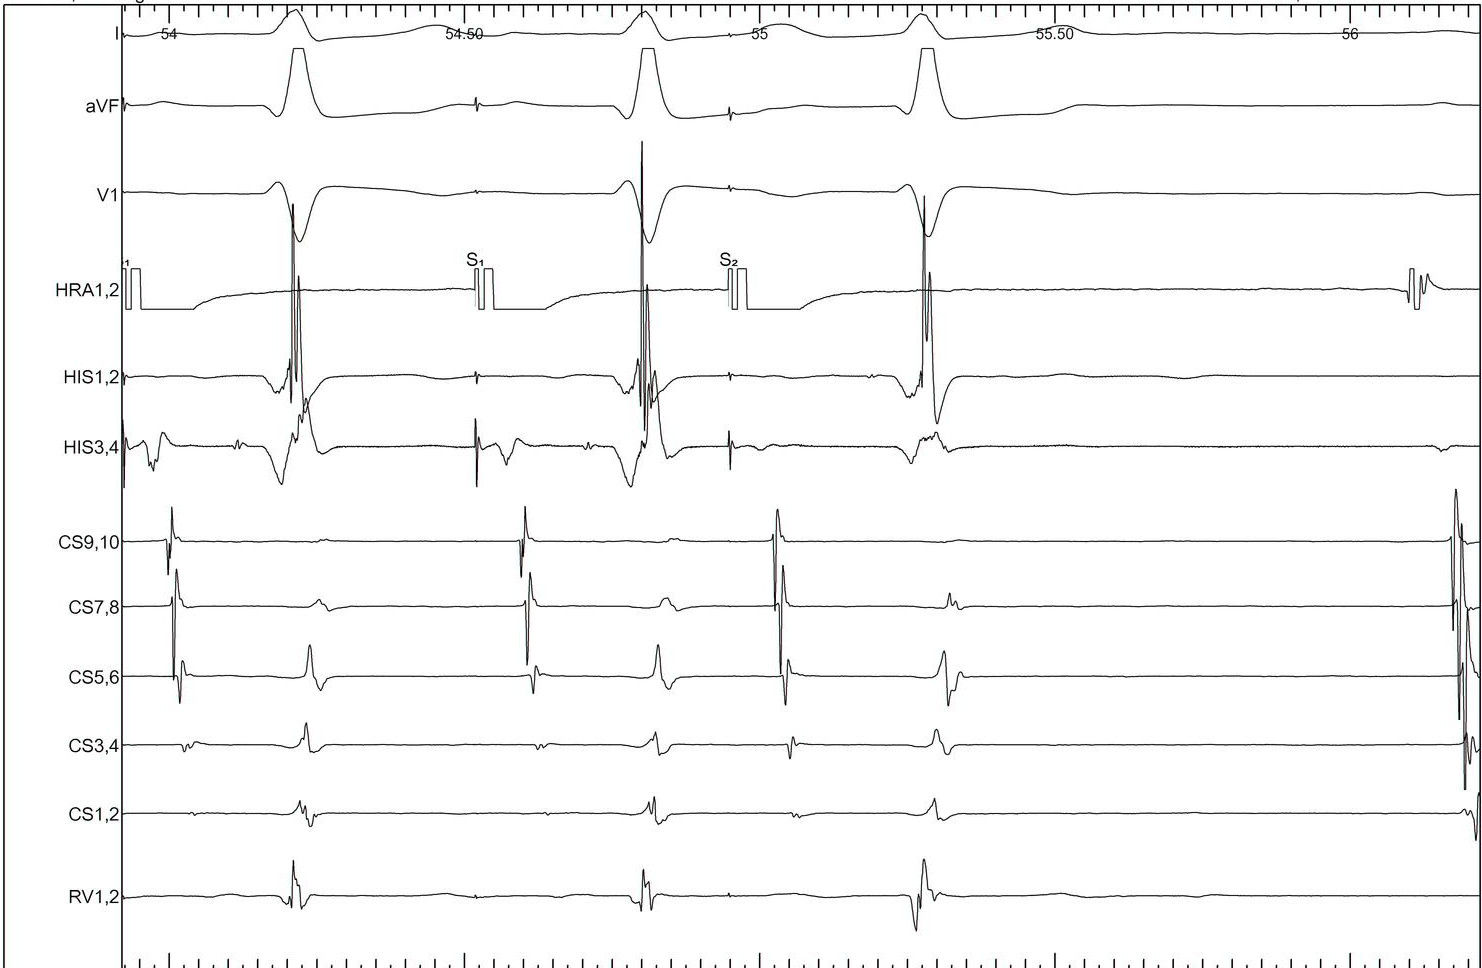

Differential pacing

• VA interval during pacing from apex and base

• Shorter from apex for nodal conduction

• Shorter from base for AP conduction

RV apex pacing

rv_apex_va.jpg

RV base pacing

rv_base_va.jpg